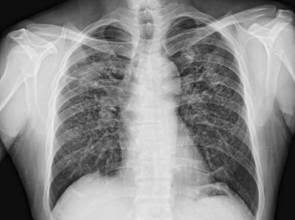

台中1名55歲鑄造工江先生,從事鑄造業脫膜工已22年,工作期間均未配戴口罩。近年常有咳嗽、痰多等類似感冒的症狀,起初不以為意,但治療服藥仍不見改善,轉至醫院經胸部X光發現雙肺已呈現第四型「塵肺症」的樣態。江先生很訝異,「塵肺症,不是礦工才會得的病嗎?」